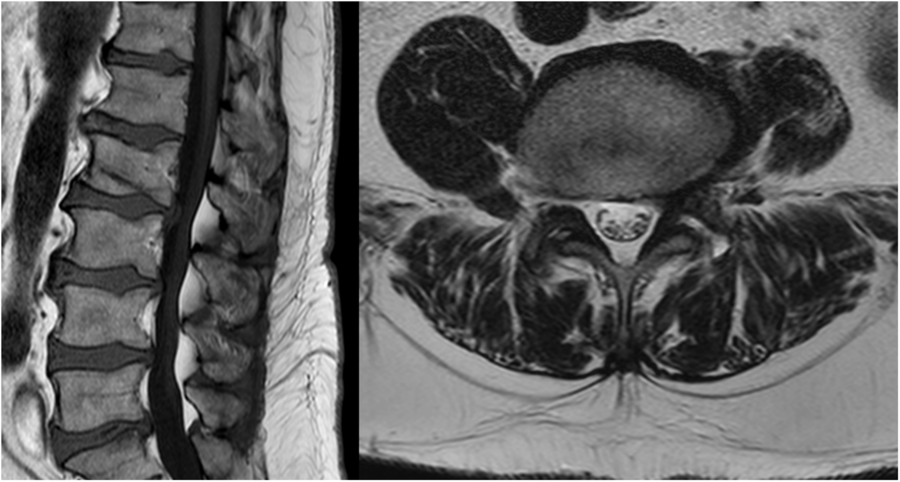

The patient was submitted to magnetic resonance imaging (MRI) of the lumbar spine that revealed a severe circumferential compression of the dural sac (from L2 to S1) caused by a relevant hypertrophy of the intracanal epidural fat (Figure 1). These findings are the characteristics of spinal epidural lipomatosis (SEL), grade 2 according to Borré, a condition already known as a rare cause of spinal stenosis.Reference Fassett and Schmidt1,Reference Borré, Borré, Aude and Palmieri2 In a previous MRI, performed 5 years before the weight gain (BMI = 33 kg/m2), for low-back pain, when claudication symptoms were not present, the epidural fat was well represented but significantly less voluminous (grade 1) (Figure 2).

Figure 2: In an MRI study (T1w sagittal image on the left and T2w axial image on the right), performed 5 years before the weight gain, the epidural fat was significantly less voluminous.